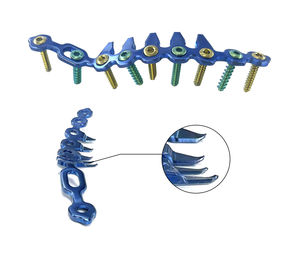

... PIONEERスモールインスツルメントシステムと組み合わせて使用するプレート&スクリューシステムです。 ...

NORMMED Medical Devices

... PIONEERスモールインスツルメントシステムと組み合わせて使用するプレート&スクリューシステムです。 ...

NORMMED Medical Devices

... PIONEERスモールインスツルメントシステムと組み合わせて使用するプレート&スクリューシステムです。 ...

NORMMED Medical Devices